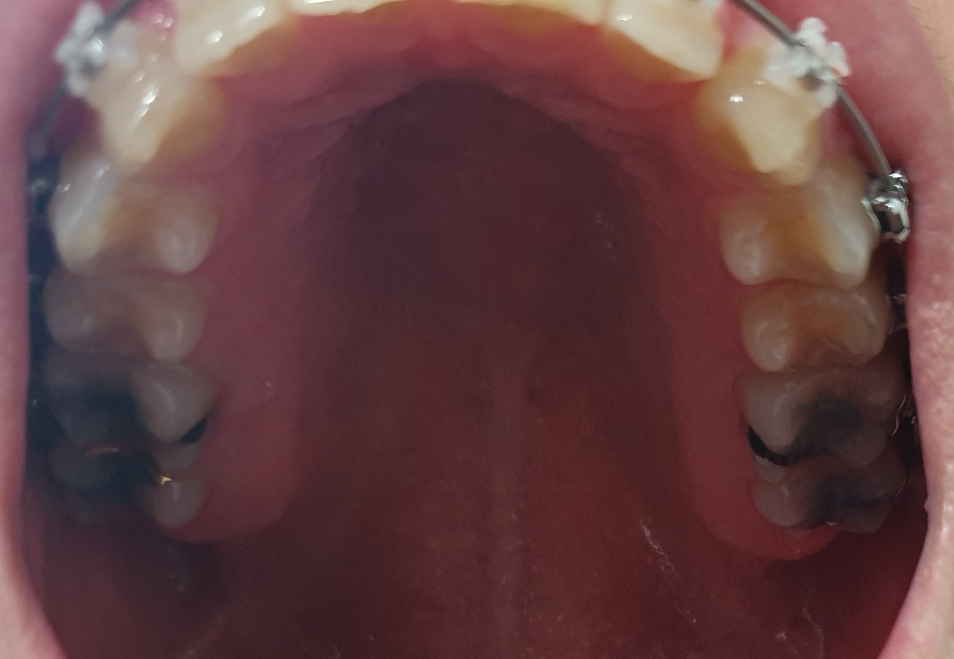

가기 전 사진입니다. 월치료 갔다오면 한 이틀 아프고 괜찮다가 3주 지나면 치아들이 움직이는 거 같은 느낌이에요.

오늘은 가서 진료보기 전 치석 제거 먼저 했어요. 양치질 잘 하라고 얘기 들었어요.. 열심히 한다고 하는데ㅎㅎ

그리고 위의 와이어는 그대로 두고 아래 와이어는 어금니까지 끼우고 두꺼운 걸로 바꿨어요. 위 아래가 맞물려서 장치 좀 다듬고 바이트블럭 더 올렸어요.

아래는 갔다와서 하루 뒤 사진이에요.